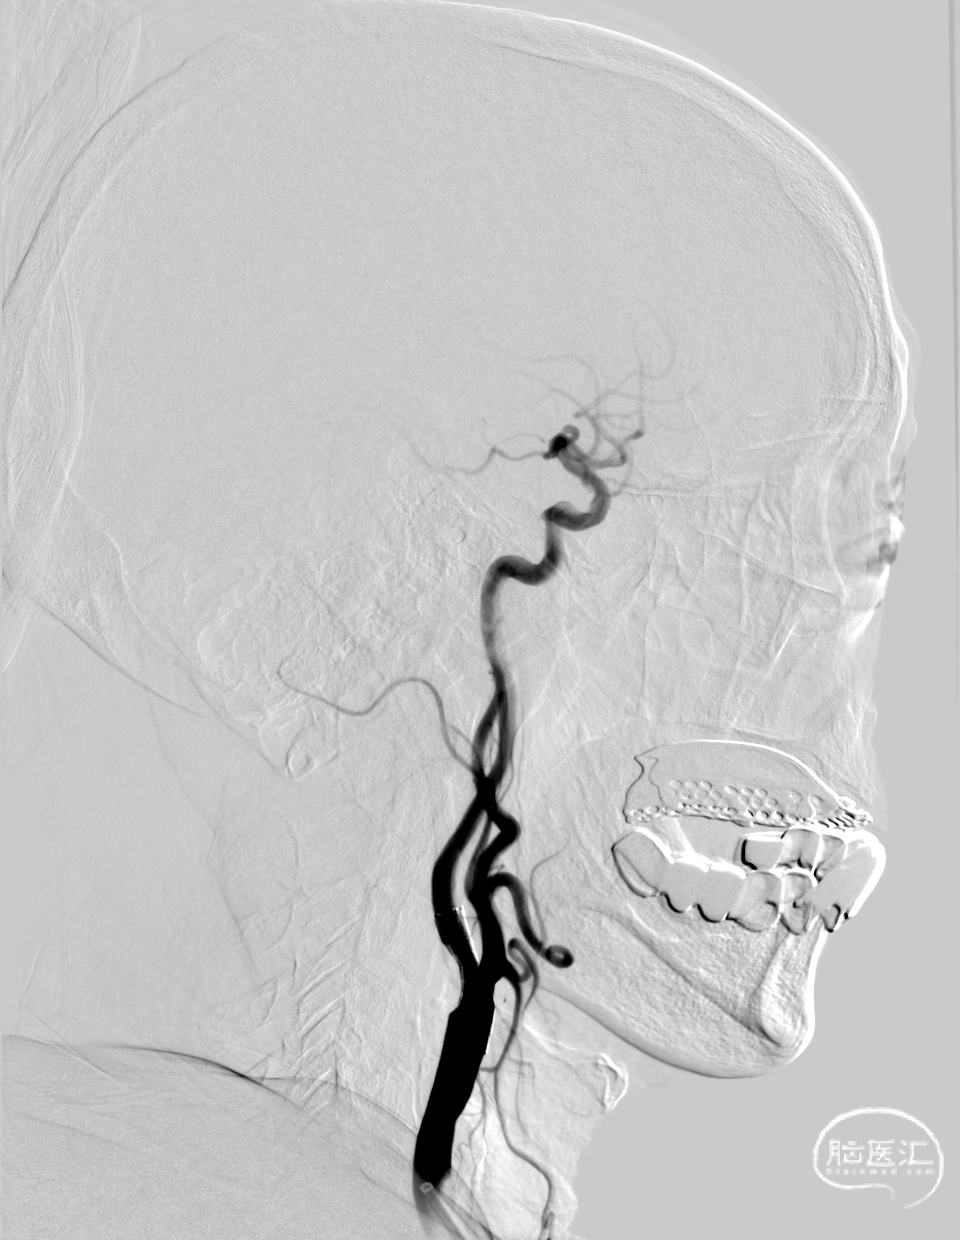

术前造影

90%狭窄

术后造影。